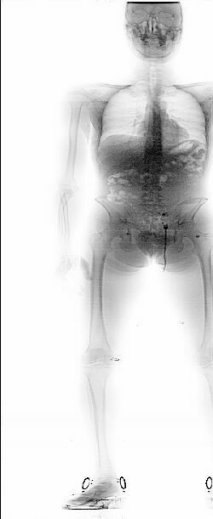

Das folgende Bild wurde mit einer Strahlenbelastung von weniger als 300 Microrem gemacht. Damit ist es bereits möglich in den Körper hineinzusehen und Gegenstände, die sich innerhalb des Körpers befinden, zu erkennen. Unter anderem verschluckte Drogenpäckchen (im Bild unterhalb des Brustkorbs zu sehen). In diesem Zusammenhang ist zu bemerken, daß in einigen Bundesländern Verdächtigen mit Gewalt Brechmittel verabreicht werden, um vermutete Drogen aus dem Körper zu befördern. Dabei kam es mehrfach zu Todesfällen.